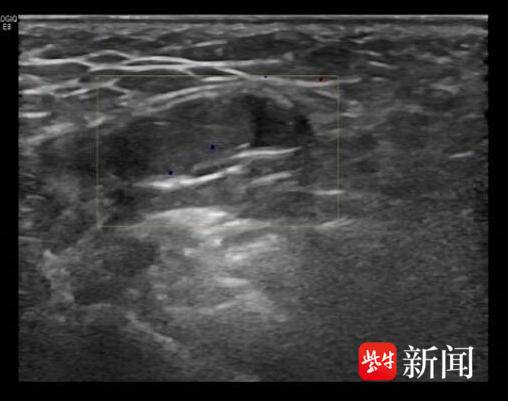

左侧腹股沟区*丸睾**

我们都知道,正常男性有双侧*丸睾**,1岁的洋洋为何只能摸到一侧*丸睾**,另一个去哪儿了呢?超声检查给出了答案,B超提示:左侧阴囊内未见*丸睾**回声,于左侧腹股沟区体表标记处见*丸睾**回声。没错,这枚消失的“蛋蛋”,就悄悄躲在腹股沟那儿呢!